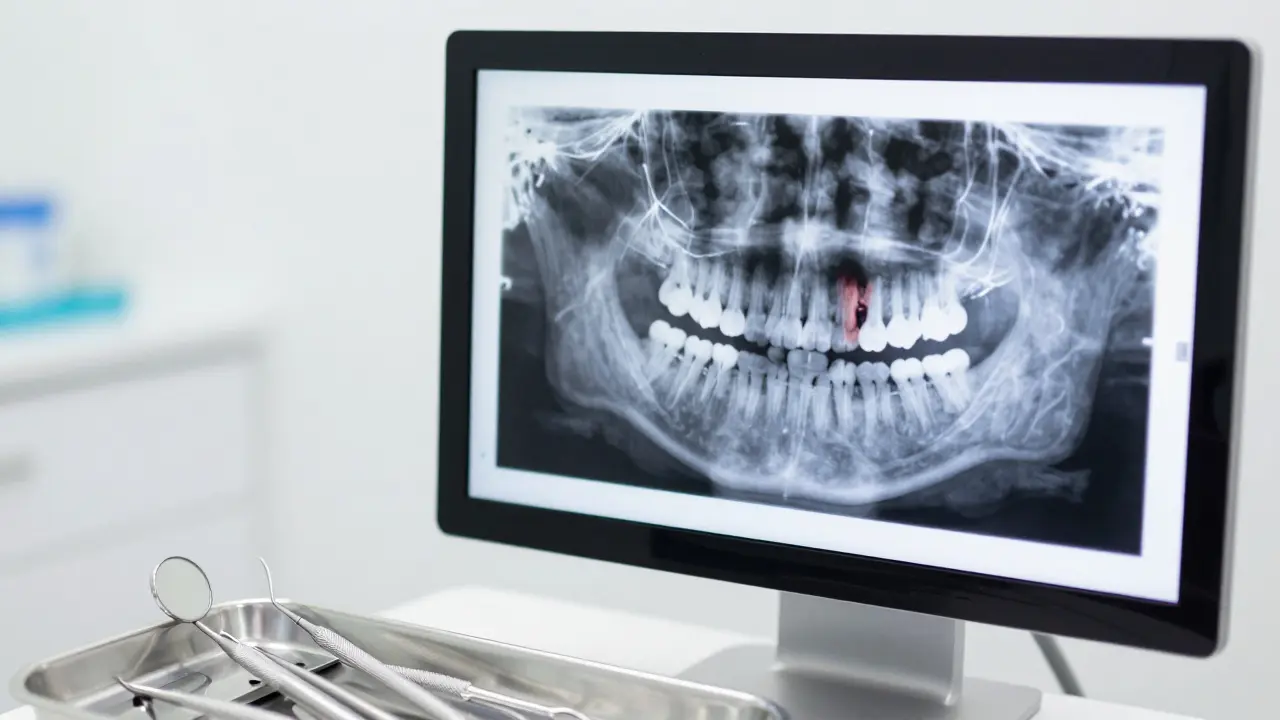

Digitální rentgen zubu na monitoru v moderní zubní ordinaci.